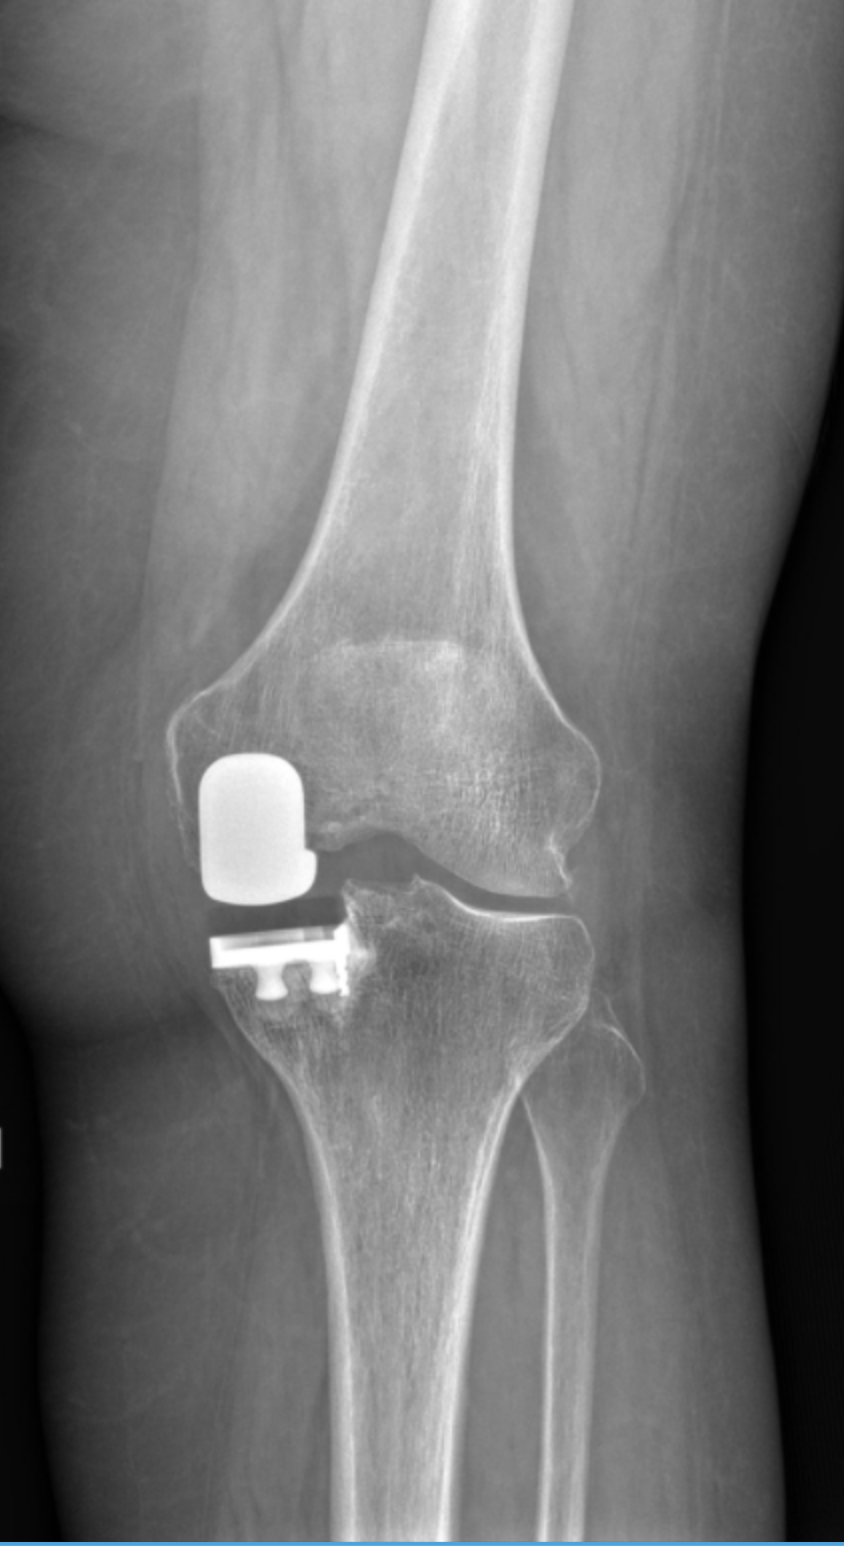

Dr. Movassaghi uses MAKO SmartRobotics™ to deliver customized knee replacements with exceptional accuracy. This advanced system allows him to plan every detail before surgery and make precise adjustments during the procedure—helping patients experience less pain, better mobility, and a quicker recovery.